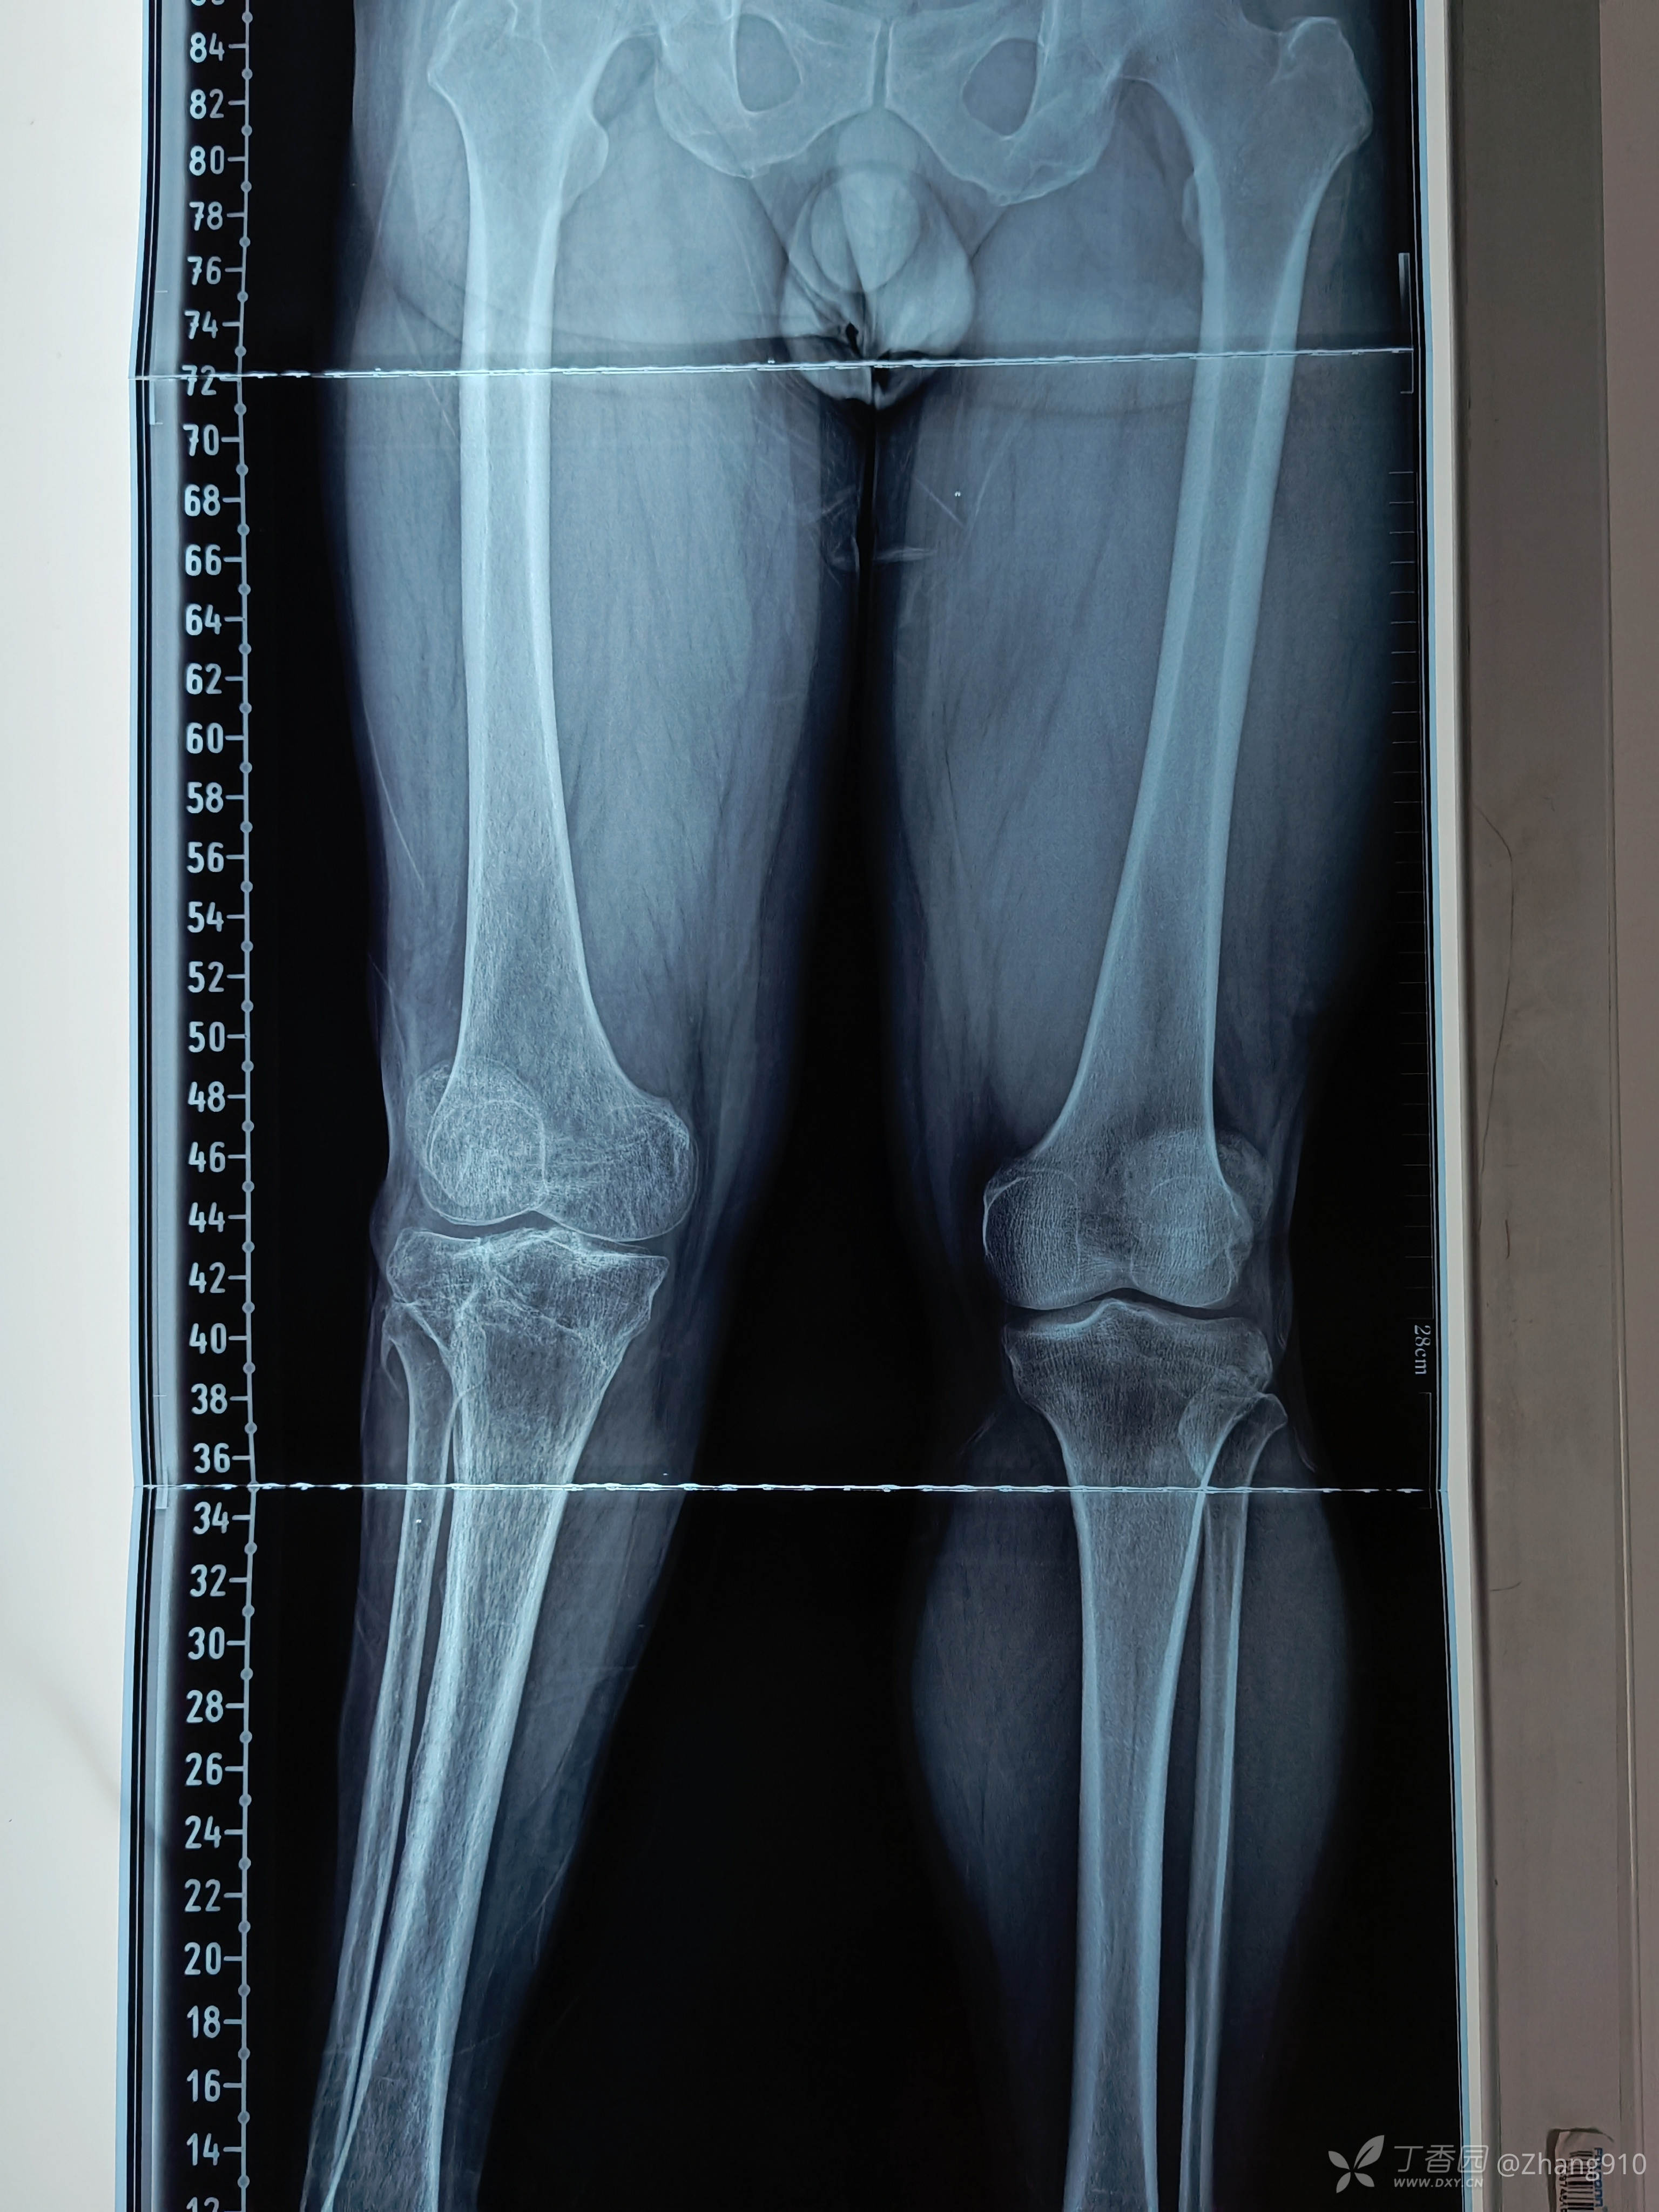

X线如下:

治疗:抬高,消炎,消肿。

目前胫骨平台情况: